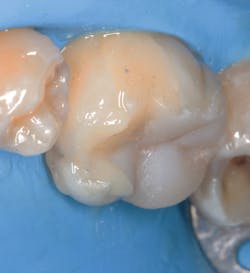

In this case we take advantage of the rubberized resin properties of Activa Presto (Pulpdent Corporation), a universal light-cure composite, to ensure that the occlusal impacts are dispersed in the best way and thus transmit the least amount of stress to the tooth (figures 6a-c–9). In addition, the biomimicking properties of Activa Presto give us the assurance that the restored area will be continuously adjusted to the margins. The restorations are cemented with Activa BioActive-Cement (Pulpdent Corporation) to ensure that the properties of the composite resin are shared by the cement (figure 10).

One of the great advantages in this technique is that the contraction of the restorative material will occur in the model stage and not in the dentition. This is very important to understand. The gap that will appear will have no clinical significance. When it is cemented with a suitable material, the restoration will be absolutely sealed to the tooth (figure 11).